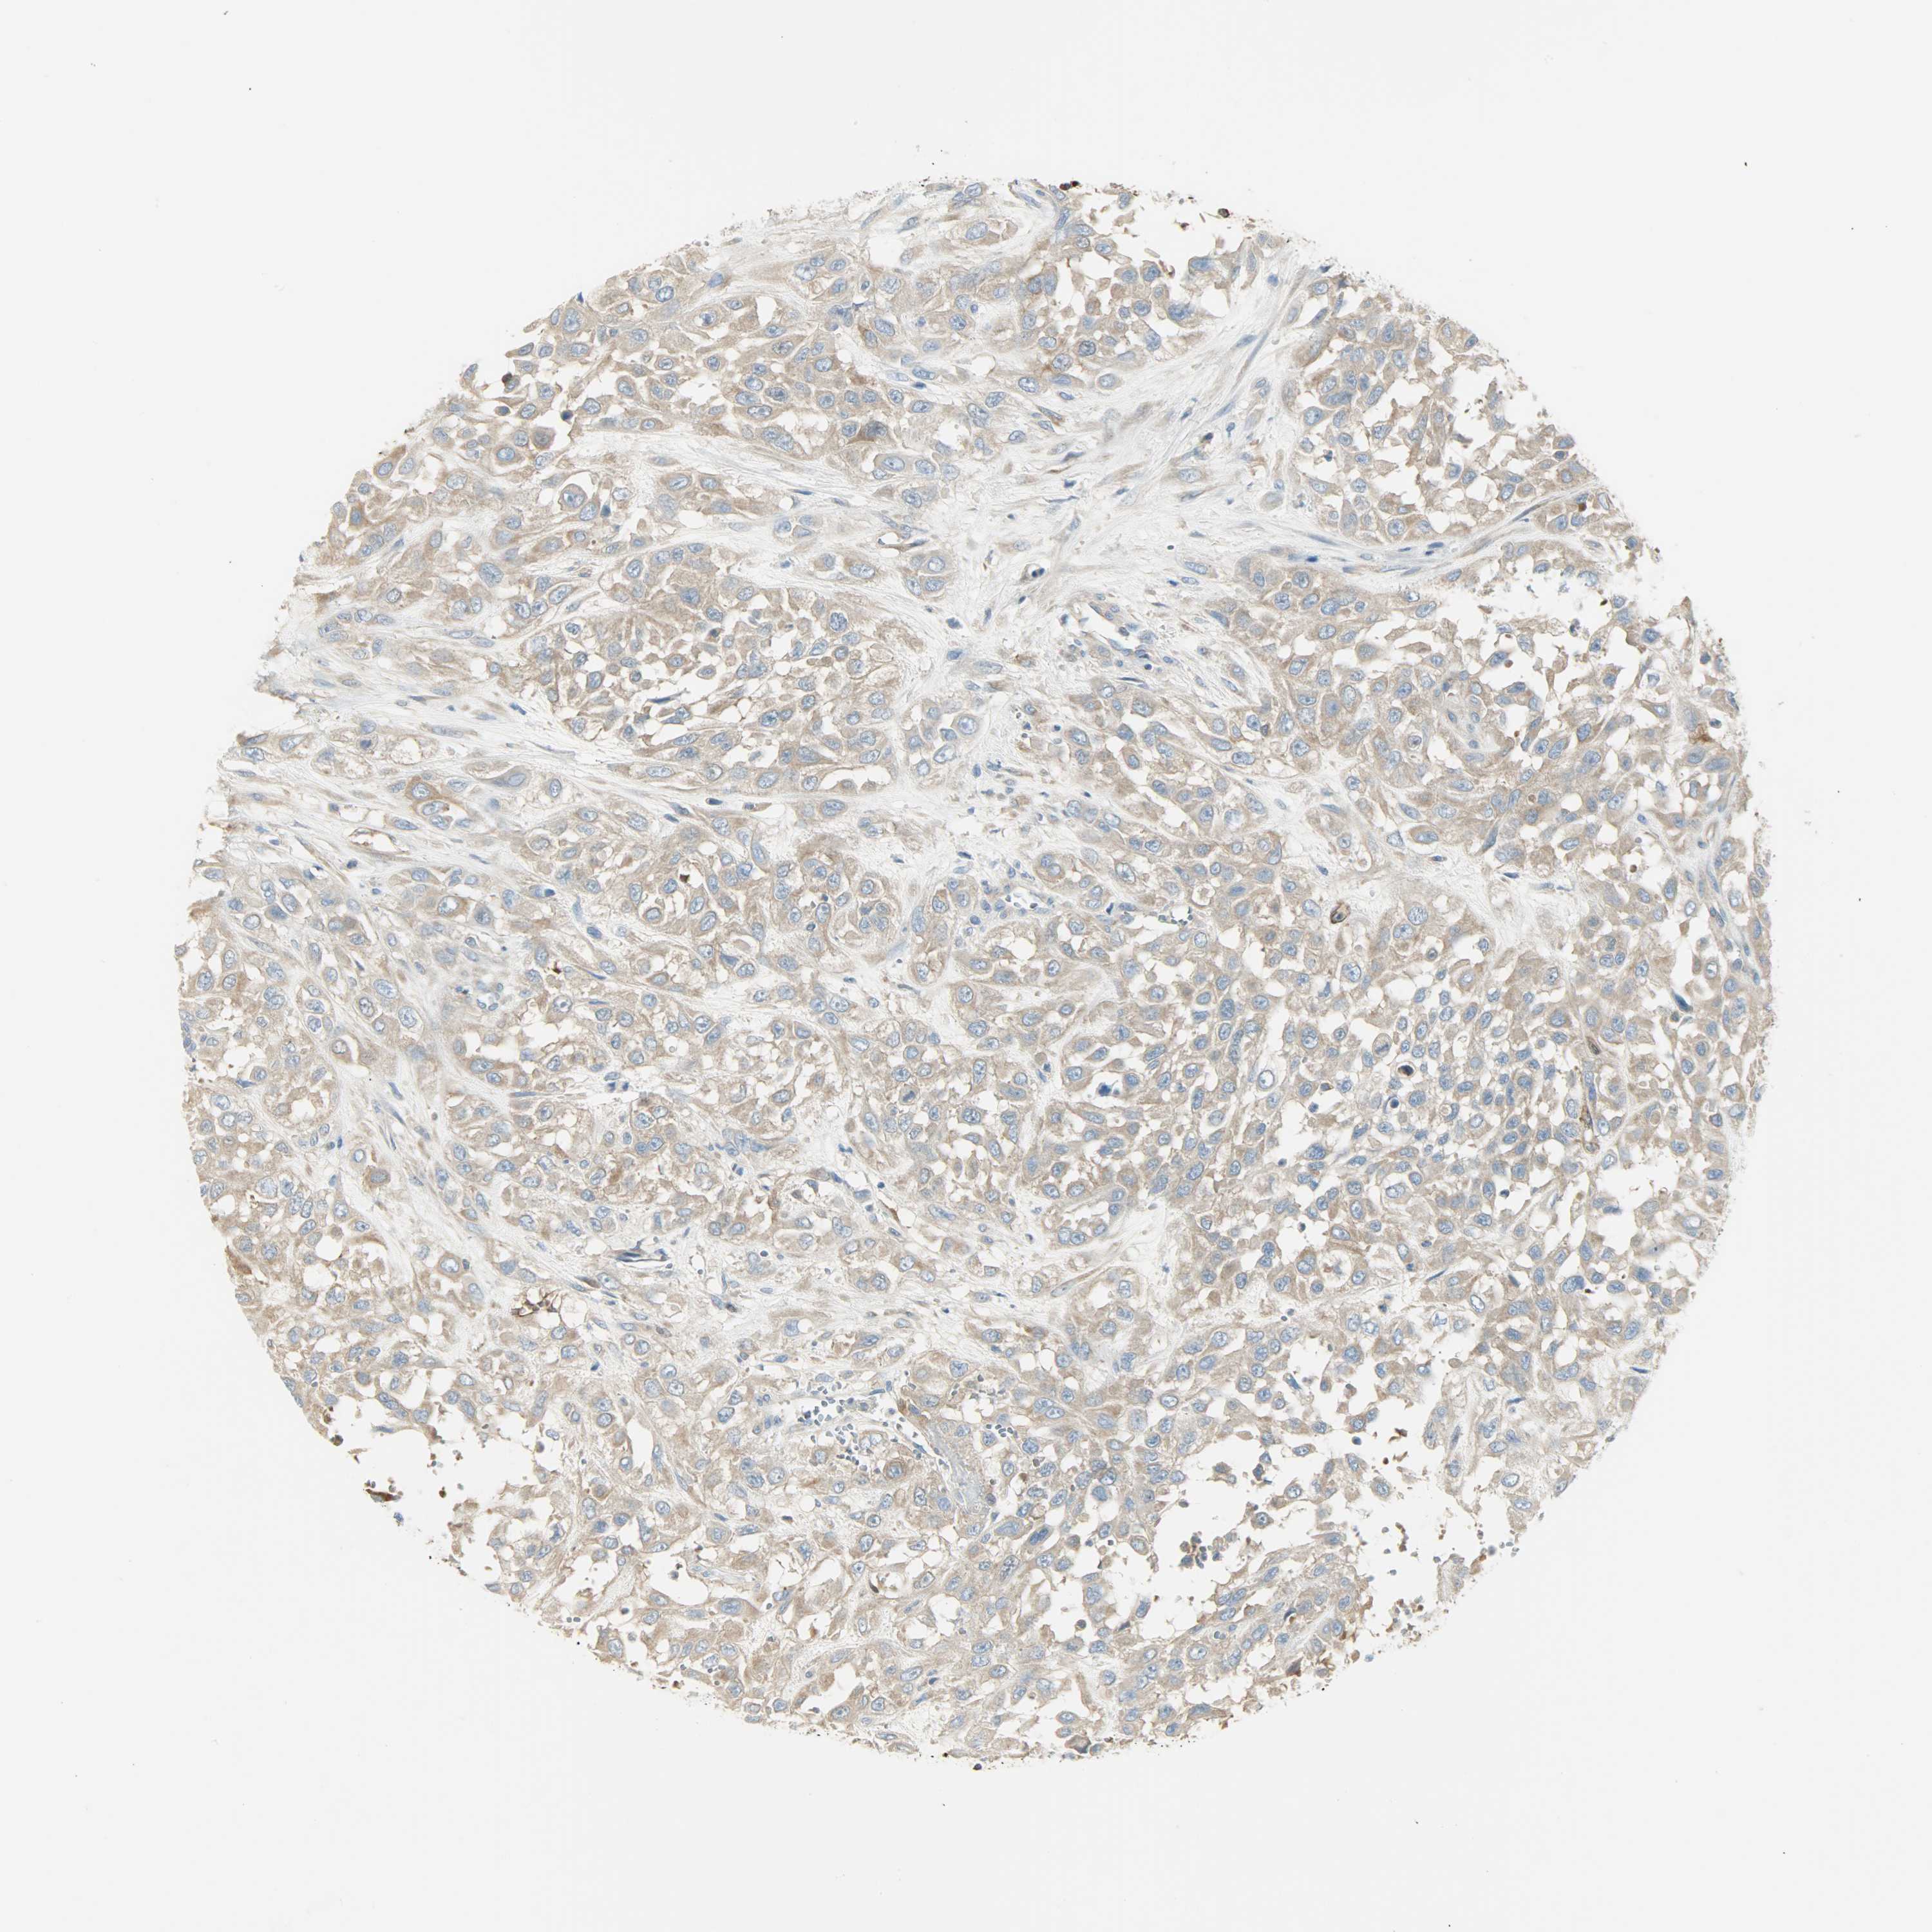

UROTHELIAL CANCER - Protein expressioni

A mouse-over function shows sample information and annotation data. Click on an image to view it in a full screen mode. Samples can be filtered based on level of antibody staining by selecting one or several of the following categories: high, medium, low and not detected. The assay and annotation is described here.

Note that samples used for immunohistochemistry by the Human Protein Atlas do not correspond to samples in the TCGA dataset.

Antibody stainingi

Antibody staining in the annotated cell types in the current human tissue is reported as not detected, low, medium, or high, based on conventional immunohistochemistry profiling in selected tissues. This score is based on the combination of the staining intensity and fraction of stained cells.

Each image is clickable and will lead to virtual microscopy that enables deeper exploration of all samples and also displays staining intensity scores, fraction scores and subcellular localization as well as patient and tissue information for each sample.

Antibody HPA005573

Staining

High

Medium

Low

Not detected

Intensity

Strong

Moderate

Weak

Negative

Quantity

>75%

75%-25%

<25%

None

Location

Nuclear

Cytoplasmic/membranous

Cytoplasmic/membranous,nuclear

Urothelial carcinoma, High grade

Urothelial carcinoma, Low grade